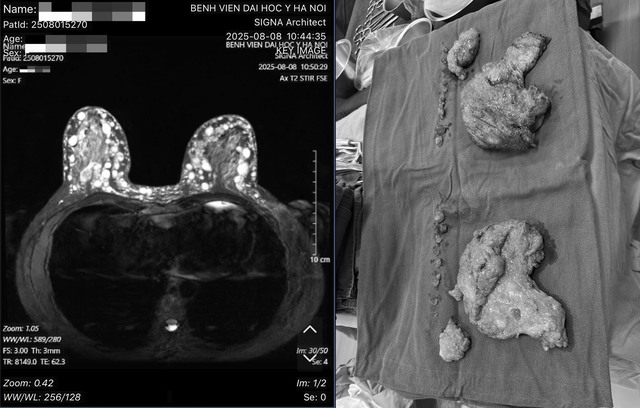

Bác sĩ Hoàng Văn Hồng (Trưởng Khoa Phẫu thuật tạo hình thẩm mỹ, Bệnh viện Đại học Y Hà Nội) cho biết đây là một ca bệnh rất đặc biệt, và hiếm gặp. Qua thăm khám, xét nghiệm và các hình ảnh chụp chiếu, bác sĩ xác định bệnh nhân bị u hạt silicon hai bên ngực hay còn gọi là siliconoma, thâm nhiễm toàn bộ tổ chức tuyến vú hai bên, đến các tổ chức mỡ dưới da, trung bì da, hay sâu đến lớp cân cơ ngực lớn, là biến chứng của việc tiêm silicon lỏng. Bên cạnh đó, bệnh nhân cũng từng tiêm silicon ở vùng má và đùi, đều đã xuất hiện các cục siliconoma ở vùng má và chân. Tuy nhiên ở hai bên ngực các tổn thương đã tiến triển gây biến chứng, các u hạt silicon lan rất sát tới vùng da, cần giải quyết trước. Nếu để lâu hơn, các hạt này tiếp tục đẩy ra sẽ dẫn đến nguy cơ nhiễm trùng, thậm chí hoại tử da vùng ngực.

"Trường hợp này bắt buộc các bác sĩ phải phẫu thuật xử lý u hạt silicon và bệnh nhân sẽ được các bác sĩ tạo hình lại vòng 1 trong cùng một lúc" - bác sĩ Hồng thông tin.

Ca phẫu thuật diễn ra hơn 7 giờ đồng hồ. Kíp phẫu thuật từ Bệnh viện Đại học Y Hà Nội gồm nhiều y bác sĩ đã phối hợp nhịp nhàng, ăn ý các kỹ thuật khó để lấy các hạt silicon ra khỏi vùng ngực bệnh nhân, sau đó tiến hành tạo hình vùng ngực.

Sau phẫu thuật, sức khỏe bệnh nhân ổn định, hai bên ngực đã được tái tạo trở về như bình thường, đáp ứng được các yêu cầu cả về hình dáng, chức năng thẩm mỹ của bầu ngực.